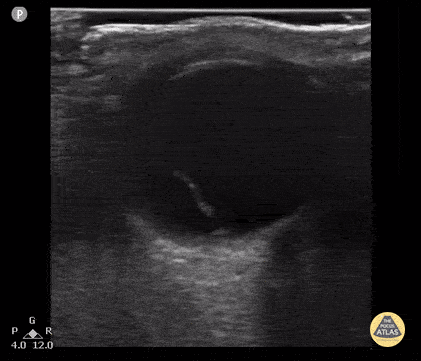

16 year old with retinal detachment (tethered to base of globe) after nerf gun injury. Note fixation point at base of the eye originating from optic nerve. Contributor: Antonio Riera, MD